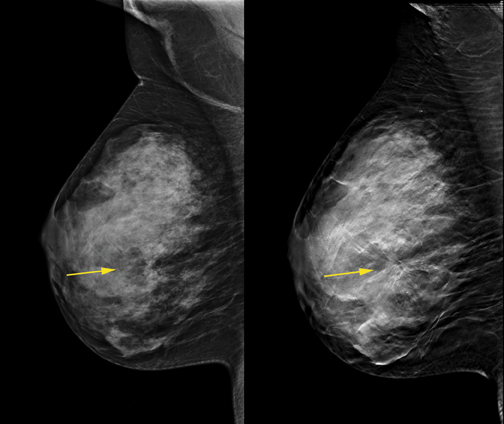

- Η HOLOGIC είναι η μόνη εταιρία που διαθέτει έγκριση από FDA σχετικά με την υπεροχή της συγκεκριμένης τεχνικής τομοσύνθεσης έναντι της κλασσικής 2D ψηφιακής μαστογραφίας και ειδικά για τις γυναίκες με πυκνούς μαστούς (FDA indication of equivalent/superior to FFDM).

Επισημαίνουμε ότι είναι εντελώς διαφορετικό να αναγράφεται στην κλινική ένδειξη FDA του εκάστοτε μηχανήματος (Physician Labelling) ότι η τεχνολογία τομοσύνθεσης προορίζεται για την ίδια κλινική εφαρμογή με την συμβατική ψηφιακή μαστογραφία και εντελώς διαφορετικό να αναγράφεται ότι η συγκεκριμένη τεχνολογία τομοσύνθεσης προορίζεται να παρέχει μια ανώτερη κλινικά εξέταση με μεγαλύτερη διαγνωστική ακρίβεια συγκριτικά με την 2D μαστογραφία και ειδικά για τους πυκνούς μαστούς , όπως μόνο στον SELENIA DIMENSIONS.

Ο ψηφιακός μαστογράφος ΤΟΜΟΣΥΝΘΕΣΗΣ που λειτουργεί στο κέντρο μαστού είναι ο μοναδικός με τη χρήση του οποίου έχει αποδειχθεί από πολυάριθμες ανεξάρτητες πολυκεντρικές κλινικές μελέτες ότι εξασφαλίζεται αύξηση της διαγνωστικής ευαισθησίας και ειδικότητας της εξέτασης μαστογραφίας, αύξηση ανίχνευσης των αληθώς καρκινικών ευρημάτων και ταυτόχρονη μείωση των ψευδώς υπόπτων ευρημάτων.

Ειδικότερα από τουλάχιστον 200 δημοσιευμένες κλινικές μελέτες (π.χ. OSLO Breast Screening Trial), προέκυψε ότι με την χρήση του Ψηφιακού Μαστογράφου SELENIA DIMENSIONS 3D για τον συνδυασμό 2D και 3D ψηφιακής μαστογραφίας εξασφαλίζεται:

- 20-65% αύξηση στην ανίχνευση των διηθητικών καρκίνων

- 27% αύξηση στην ανίχνευση καρκίνων (διηθητικών και μη διηθητικών)

- 15% μείωση σε ψευδώς θετικά αποτελέσματα